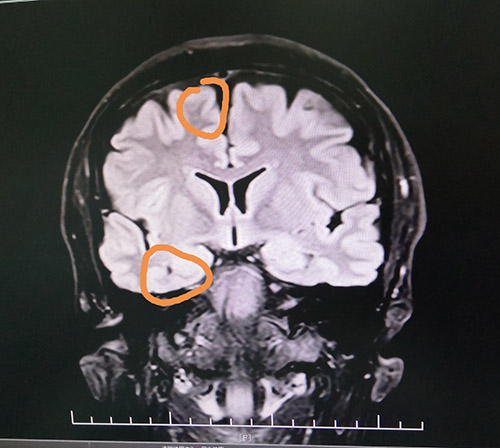

頭顱海馬MRS檢查顯示:右側(cè)海馬Cho/NAA+Cr=0.5;左側(cè)海馬Cho/NAA+Cr=0.56。PET-CT檢查顯示,右側(cè)顳區(qū)FDG代謝減低。視頻腦電圖(VEEG)顯示,在清醒狀態(tài)下,額區(qū)和顳區(qū)顯著,各導(dǎo)聯(lián)較多異常波陣發(fā)出現(xiàn)。在睡眠狀態(tài)下,顳區(qū)有少許高-極高波幅尖波、尖慢波左右不同步單發(fā)、偶波及額極、額區(qū)(右側(cè)顯著、多以睡眠期出現(xiàn))。

藍(lán)十字腦科功能神經(jīng)外科主任楊忠旭博士認(rèn)真查看了劉先生各項(xiàng)檢查報(bào)告并聽取相關(guān)病情匯報(bào),認(rèn)為患者腦組織結(jié)構(gòu)發(fā)生病變,引起癲癇發(fā)作,經(jīng)系統(tǒng)藥物治療無任何改善,應(yīng)用現(xiàn)代神經(jīng)影像學(xué)技術(shù)和電生理監(jiān)測(cè)技術(shù),能明確引起癲癇發(fā)作的的“責(zé)任病變”。

在征得患者家屬同意后,10月28日上午,楊忠旭博士在助手杜立功及醫(yī)護(hù)團(tuán)隊(duì)協(xié)助下為劉先生進(jìn)行了“癲癇病灶切除術(shù)”手術(shù)。由于患者患有高血壓、腦萎縮,腦血管異常脆弱,且局部腦組織結(jié)構(gòu)異常,多處異常放電部位,為手術(shù)帶來挑戰(zhàn),手術(shù)中需要格外小心。在全程腦電監(jiān)測(cè)下,楊博士處之泰然,游刃有余,在助手密切配合下,為患者切除了顳葉、海馬和額葉病灶。癲癇病灶切除后,再次監(jiān)測(cè)腦區(qū),無異常放電,手術(shù)成功。緊接著徹底止血,嚴(yán)密縫合硬腦膜,復(fù)位骨板……緊張的手術(shù)終于結(jié)束。